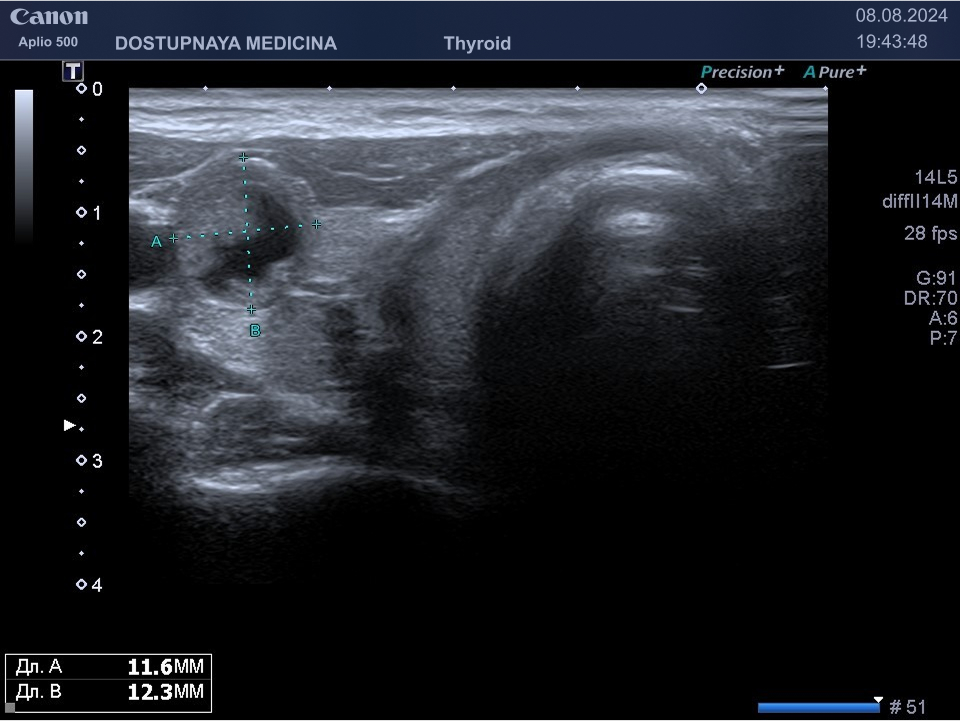

В ультразвуковой диагностике существует классификация образований щитовидной желзы по TIRADS, которая по различным критериям определяет степень онкоопастности того или ионого узла. При оценке учитывается эхоструткура образования ( кистозная, губчатая, солидная или солидно-кистозная), эхогенность ( анэхогенное, гиперэхогенное, гипоэхогенное), пространственная ориентация горизонтальная, вертикальная, неопределённая), контуры образования (ровные, дольчатые, зазубренные с острыми углами), наличие эхогенных включений( макрокальцинаты, микрокальцинаты, периферическая кольцевидная кальцификация). В зависимости от этих критериев выделяют различные категориии объёмных образований в щитовидной железе:

TIRADS 3 – низко подозрительное образование, требующие динамическое наблюдение и тонкоигольной биопсии при размерах узла больше 2.5 см.

TIRADS 4 – умеренно подозрительное образование, требующие динамическое наблюдение и тонкоигольной биопсии при размерах узла больше 1.5 см.

TIRADS 5 – высоко подозрительное образование, требующие динамическое наблюдение и тонкоигольной биопсии при размерах узла больше 1 см.

Большинство узловых образований в щитовидной железе не нуждаются в лечении и требуют лишь наблюдения путём повторного ультразвуковых исследований.

При подозрении на озлокачествление и увеличении узла в размерах требуется тонкоигольная пункционная биопсия с полседующим цитологическим исследованием, полученного материала.